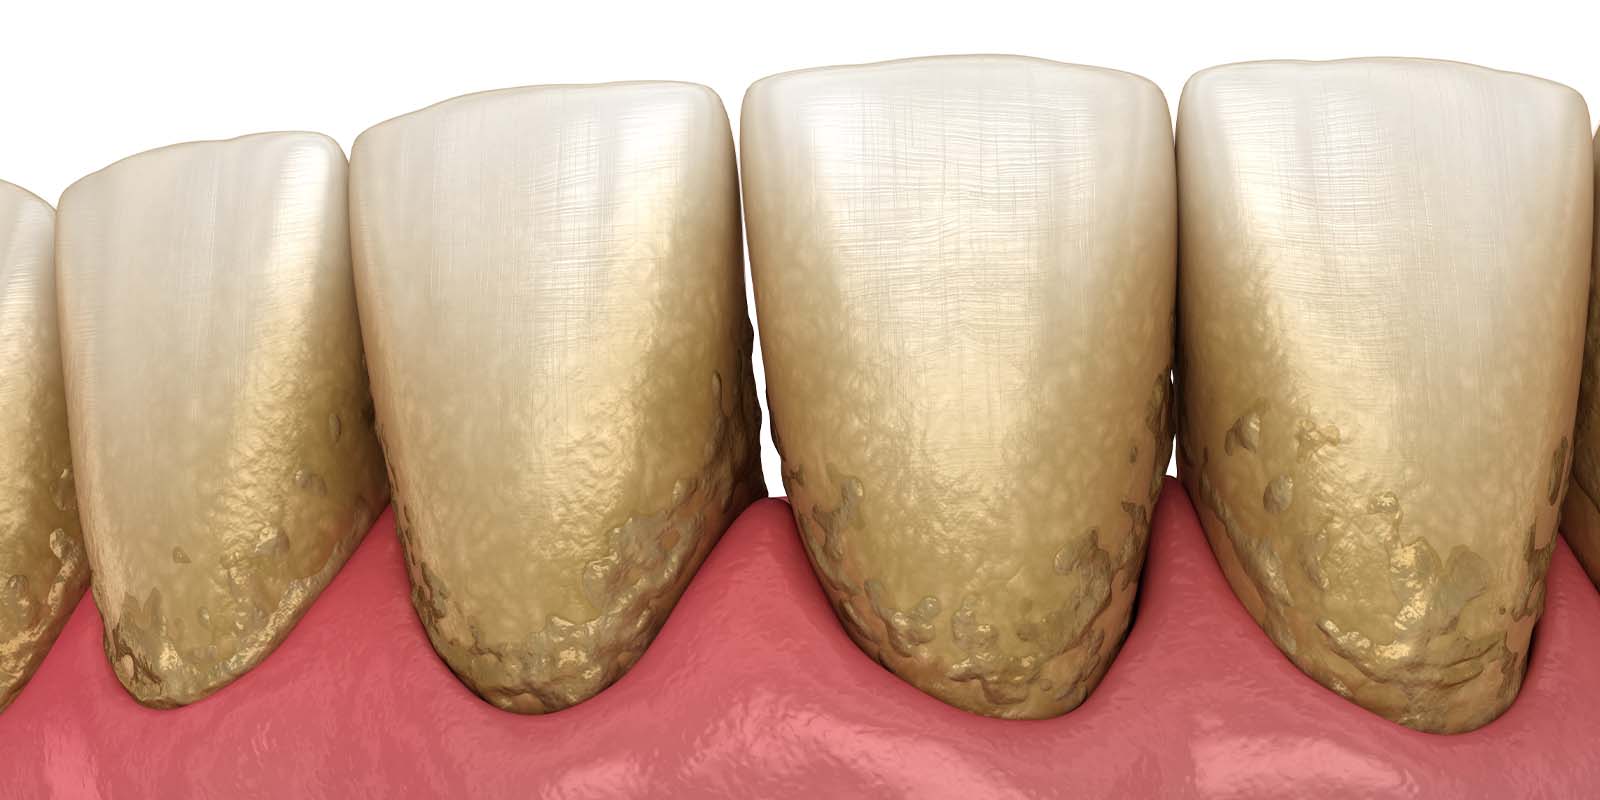

2. スケーリング(歯石除去)

歯科医院で行うクリーニングの中に含まれるもので、専用の機械や器具を使用して歯石を取り除きます。

歯石の表面にはざらつきがあり、プラークが溜まりやすくなるため定期的に除去しましょう。

スケーリングで歯石を除去する重要性

歯石は歯垢(プラーク)が石灰化したものです。

大量の細菌が含まれていますが、歯ブラシの力では除去することができません。

特に歯周病の場合は、歯ぐきの中に歯石が入り込むため、気づかずに放置してしまう方も少なくないのです。

歯周病を悪化させないためにも、定期的なクリーニングで歯石の除去をおすすめします。